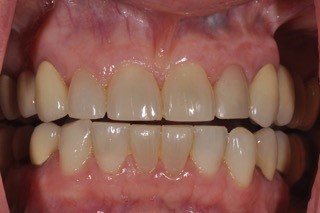

I’d like to introduce you to two patients in my practice. Caroline is a healthy, 23-year-old patient. She has a retained primary lateral incisor at tooth #10 that is decalcified and unesthetic. The tooth has undergone bone replacement and root resorption. As a result, it’s ankylosed but has acceptable bone and adequate facial prominence. An immediate implant and immediate provisional are considered the ideal treatment for replacement.

Karen is 64 years old, and her medical history is non-contributory. She, too, requires an implant at tooth #10 because of a tooth fracture from mastication. The existing tooth was deemed non-restorable. There is no periapical infection and a healthy periodontium. An implant was planned as the replacement treatment.

Both Caroline’s and Karen’s lateral incisors were removed, and immediate implants were placed. Although the implant surgeons were different, they were both long-time members of my interdisciplinary team and had significant implant placement experience. Both implants were torqued to 50 Ncm at the time of placement. Provisionals were then placed by me that same day.

The implants were not in occlusion, and instructions for mastication and maintenance were provided. Neither patient wore occlusal appliances or night guards. However, Caroline routinely wore Essex retainers, which her orthodontist provided. I had fabricated a new Essex following her implant provisional. Both implants were allowed to heal for four months before final restoration.

Following four months of healing, Karen was appointed in my office for the final restoration of the implant. The provisional was removed, without anesthesia, and the implant impression post was secured to the newly healed implant. The restorative process was uneventful, and a ceramic restoration and gold post were placed.

Alternatively, Caroline was scheduled for her implant restorative process. Again, no anesthesia was utilized. The retaining screw was loosened, and the provisional was removed. Upon tightening the impression post to the implant, Caroline winced with pain! The implant was not integrated! Why?